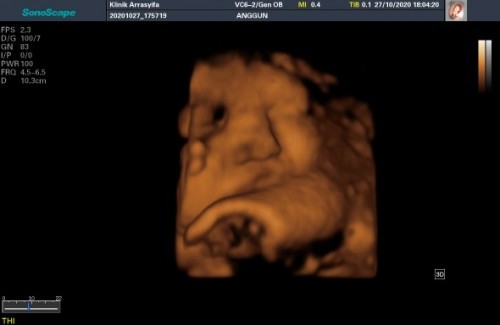

38week, baby girl 😍 Dede nya manyun 🤭